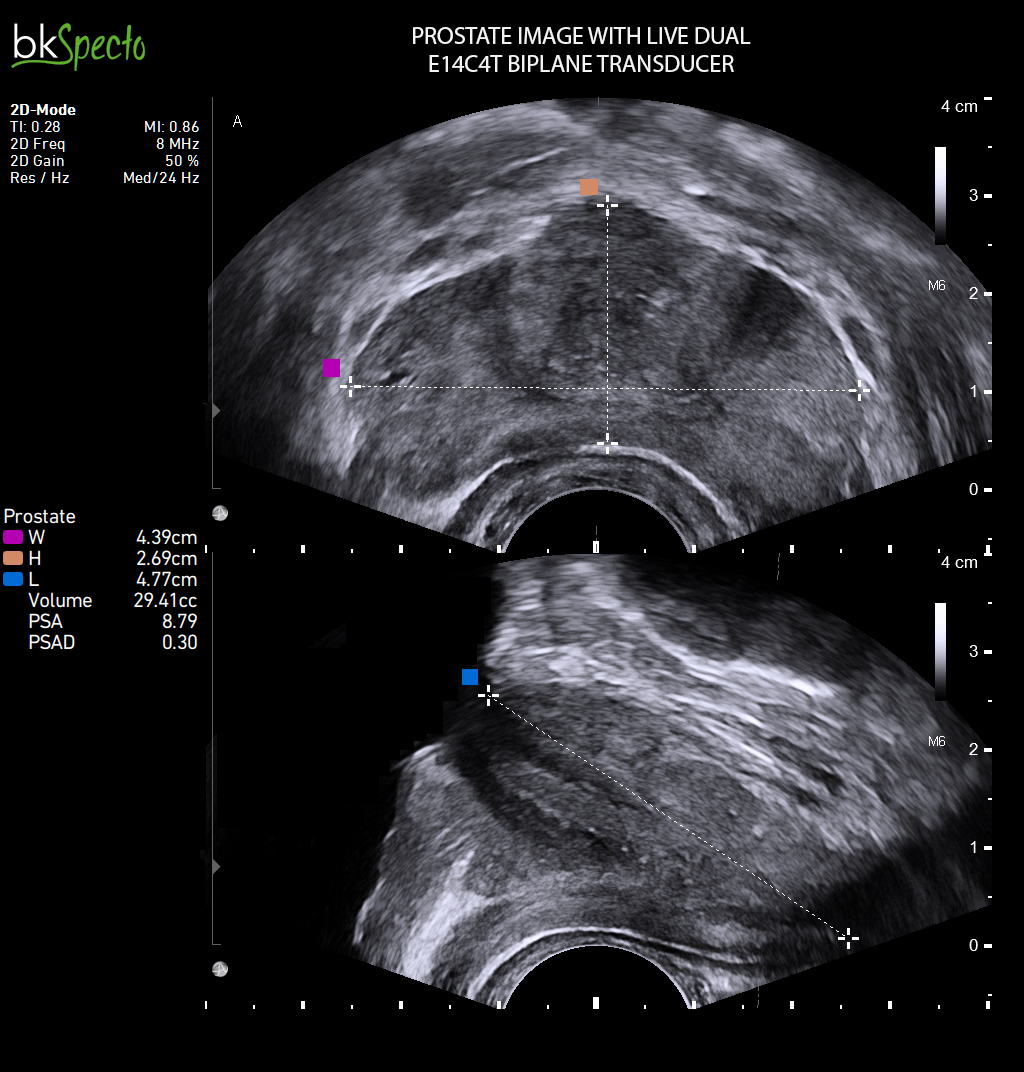

- Modul sinh thiết và điều trị u xơ tiền liệt tuyến (TUR) qua ngả trực tràng dưới dướng dẫn siêu âm _Prostate Imaging & Biopsy: Đặc biệt kỹ thuật điều trị u xơ tiền liệt tuyến bằng hạt phóng xạ (brachytherapy)

- Gá sinh thiết dùng với đầu dò siêu âm các loại